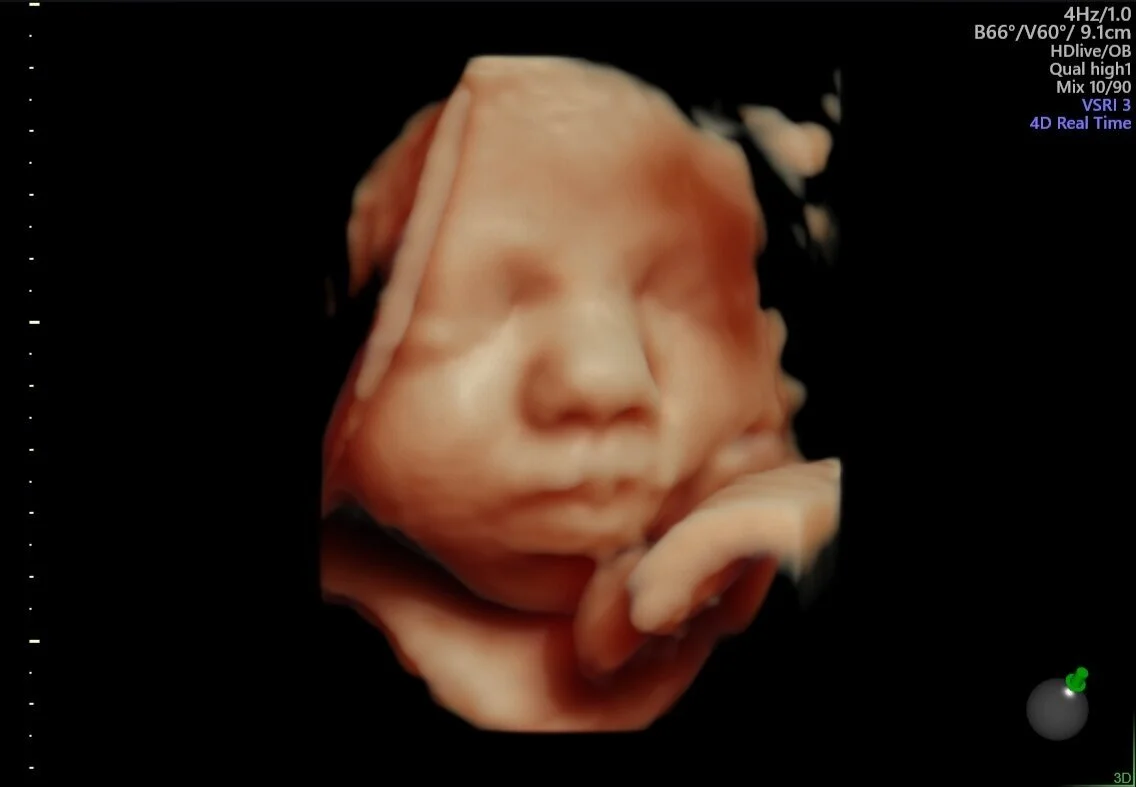

Bio Imagem Entendendo Sobre O Exame Ultrassonografia 3d 4d O Ultrassom Em 3 D Mostra Imagens Do Bebe Em Tres Dimensoes E A Melhor Parte E Que Da Para Ver O Rostinho Dele

Ultrassom 3d E 4d Conheca As Diferencas E Quando Fazer

Ultrassom 4d Mostra Detalhes Da Fisionomia Do Bebe E Movimentos Dentro Da Barriga Da Mae

Ultrassom 3d Conheca O Exame E Saiba Se Vale A Pena Fazer